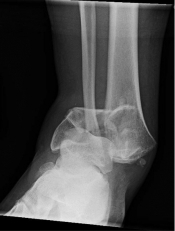

What’s the diagnosis? Gepost op 14 januari 202113 januari 2021 door netwerkvsseh What’s the diagnosis? By Dr. Erica Schramm @emdaily.cooperhealth.org Dit delen: Delen op X (Opent in een nieuw venster) X Share op Facebook (Opent in een nieuw venster) Facebook Delen op LinkedIn (Opent in een nieuw venster) LinkedIn E-mail een link naar een vriend (Opent in een nieuw venster) E-mail Afdrukken (Opent in een nieuw venster) Print Vind-ik-leuk Aan het laden... Gerelateerd